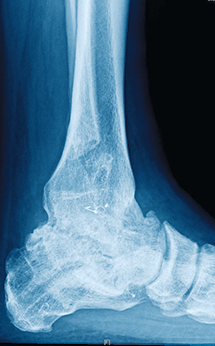

3 and 4

The patient chose to undergo ankle arthrodesis, which healed uneventfully, with good pain relief and good function for years. Ankle morphology (including the fibula) was preserved, which is essential if ever considering conversion to ankle arthroplasty.